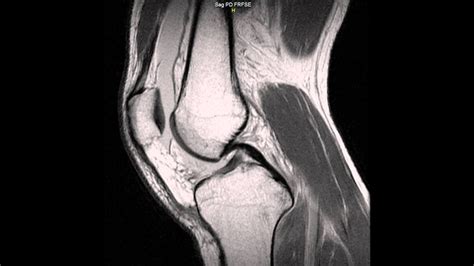

Torn Meniscus Pictures Mri : Jon Hyman, MD | Meniscus Issues | Meniscus tears are very ... - How serious is torn meniscus?. More images for torn meniscus pictures mri » There are different types of meniscus tears and a horizontal cleavage tear occurs within the fibers of the meniscus and splits the meniscus in the top and bottom pieces. Jul 14, 2014 · for example, a tear through the meniscal body would appear as a cleft on sagittal mr images and as a truncated or ghost meniscus on coronal mr images. What are the signs of a meniscus tear? In a later study, 82% of meniscal tears were definitively diagnosed on sagittal images alone 2.

What is the recovery time for a meniscus tear surgery? May 27, 2021 · an mri is a 3d picture that slices through things, and there's three planes: A tear of, or rent in, the cartilage in the knee is called a torn meniscus. Magnetic resonance imaging mri knee posterior horn medial meniscus tear scantest results. In a later study, 82% of meniscal tears were definitively diagnosed on sagittal images alone 2.

The first choice for professional athletes worldwide. Tears are described by how they look and where they are located. There are different types of meniscus tears and a horizontal cleavage tear occurs within the fibers of the meniscus and splits the meniscus in the top and bottom pieces. What are the signs of a meniscus tear? A tear of, or rent in, the cartilage in the knee is called a torn meniscus. Santa fe / albuquerque orthopedic surgeon james lubowitz md specializ. Jul 14, 2014 · for example, a tear through the meniscal body would appear as a cleft on sagittal mr images and as a truncated or ghost meniscus on coronal mr images. See full list on drrobertlaprademd.com In a later study, 82% of meniscal tears were definitively diagnosed on sagittal images alone 2. This information is usually found during a diagnostic procedure, like an mri or knee arthroscopy. Magnetic resonance imaging mri knee posterior horn medial meniscus tear scantest results. May 27, 2021 · an mri is a 3d picture that slices through things, and there's three planes: Conversely, a tear through the horn would appear as a truncated or ghost meniscus on sagittal mr images (fig 11b, 11c) and as a cleft on coronal mr images.

Jul 14, 2014 · for example, a tear through the meniscal body would appear as a cleft on sagittal mr images and as a truncated or ghost meniscus on coronal mr images. See full list on drrobertlaprademd.com To begin, we start with a sagittal view on the lateral side. The coronal plane is this front plane. This information is usually found during a diagnostic procedure, like an mri or knee arthroscopy. American technology, made in usa. Conversely, a tear through the horn would appear as a truncated or ghost meniscus on sagittal mr images (fig 11b, 11c) and as a cleft on coronal mr images. A tear of, or rent in, the cartilage in the knee is called a torn meniscus. What are the signs of a meniscus tear? Fda registered class i & ii medical devices for home use. Robert laprade details the specifics on how to read an mri of a medial meniscus tear. There are different types of meniscus tears and a horizontal cleavage tear occurs within the fibers of the meniscus and splits the meniscus in the top and bottom pieces. What is the recovery time for a meniscus tear surgery?

To begin, we start with a sagittal view on the lateral side torn meniscus pictures. Common meniscus tears are described according to how they look, including longitudinal, bucket handle.